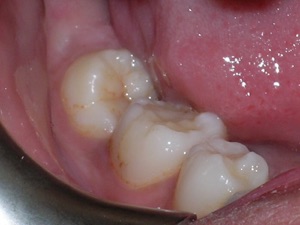

Look at the before and after of the second molar on the right side.